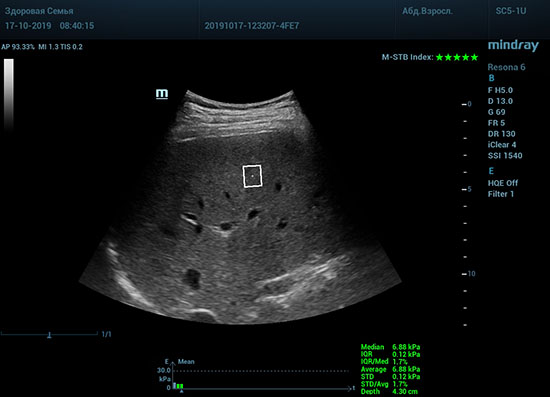

Определение плотности печени. Не ошибся ли оператор при измерении эластических свойств печени? Для оценки критериев качества предусмотрен индекс MBT, который покажет насколько «твердой» была рука оператора и двигалась ли печень. При MBT 5* рука тверда и показатели достоверны. Для оценки качества результатов используется IQR индекс, отображающий колебания показателей в точке измерения при расчете медианы. Показатели при IQR <30% считаются приемлемыми. Техника сканирования через межреберные промежутки требует размещение окна интереса на несколько сантиметром ниже капсулы, для исключения эффекта реверберации. Установка ROI на паренхиму без захвата сосудов, для исключения погрешностей измерения.

Стадия фиброза определяется по системе METAVIR Staging, построенной на данных биопсии и сопоставлении с данными эластографии. Своевременная диагностика фиброза, и начало его лечения, залог благоприятного исхода заболевания.

• METAVIRF0 – норма.